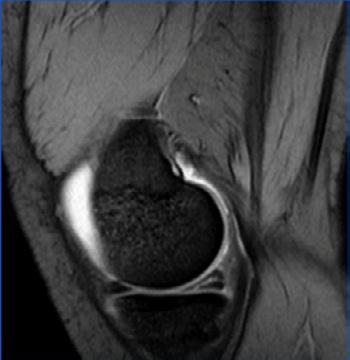

Rapport d’un examen d’IRM du genou droit généré par ChatGPT :

Un épanchement articulaire important, plus prononcé dans la région suprapatellaire. Il existe également des preuves d’une déchirure du ménisque médial, ainsi que de légères modifications dégénératives du cartilage articulaire. Le ligament croisé antérieur et le ligament croisé postérieur sont intacts. Le mécanisme extenseur est également intact. Aucune autre anomalie significative n’est observée.

■ Impression : Épanchement articulaire important et déchirure méniscale médiale du genou droit, avec de légères modifications dégénératives du cartilage articulaire.

■ Avis des radiologistes : Reconnaissance correcte de l’étude, diagnostic correct (épanchement et déchirure méniscale).